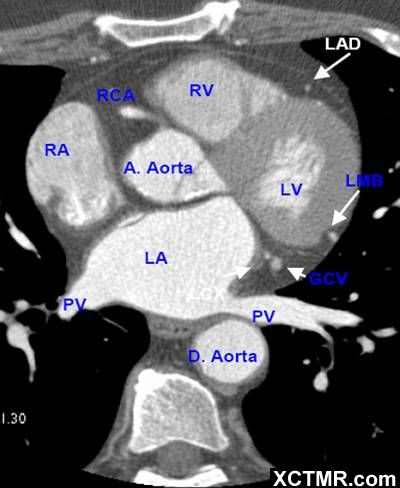

LA - Left Atrium 左心房

RA - Right Atrium 右心房

LV - Left Ventricle 左心室

RV - Right Ventricle 右心室

A. Aorta-Ascending Aorta 升主动脉

D. Aorta-Descending Aorta 降主动脉

PV - Pulmonary Vein 肺静脉

LAD - Left Anterior Descending Artery 左前降支

LMB - Left Obtuse Marginal Branch 左边缘支(钝缘支)

RCA - Right Coronary Artery 右冠状动脉

GCV –Great Cardiac Vein 心大静脉